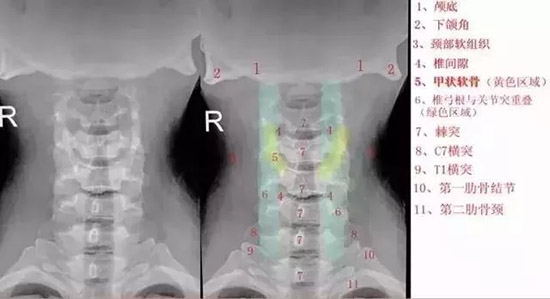

颈椎正位

颈椎正位片的临床意义在于:

1.从正位方向观察颈椎排列情况和曲度的改变;

2.观察构锥关节的结构和增生情况,从而推断椎动脉型颈椎病的发生和程度;

3.观察双侧椎弓根和棘突(都是轴位显示)之间的关系;

4.左右颈部软组织内的异常密度情况;